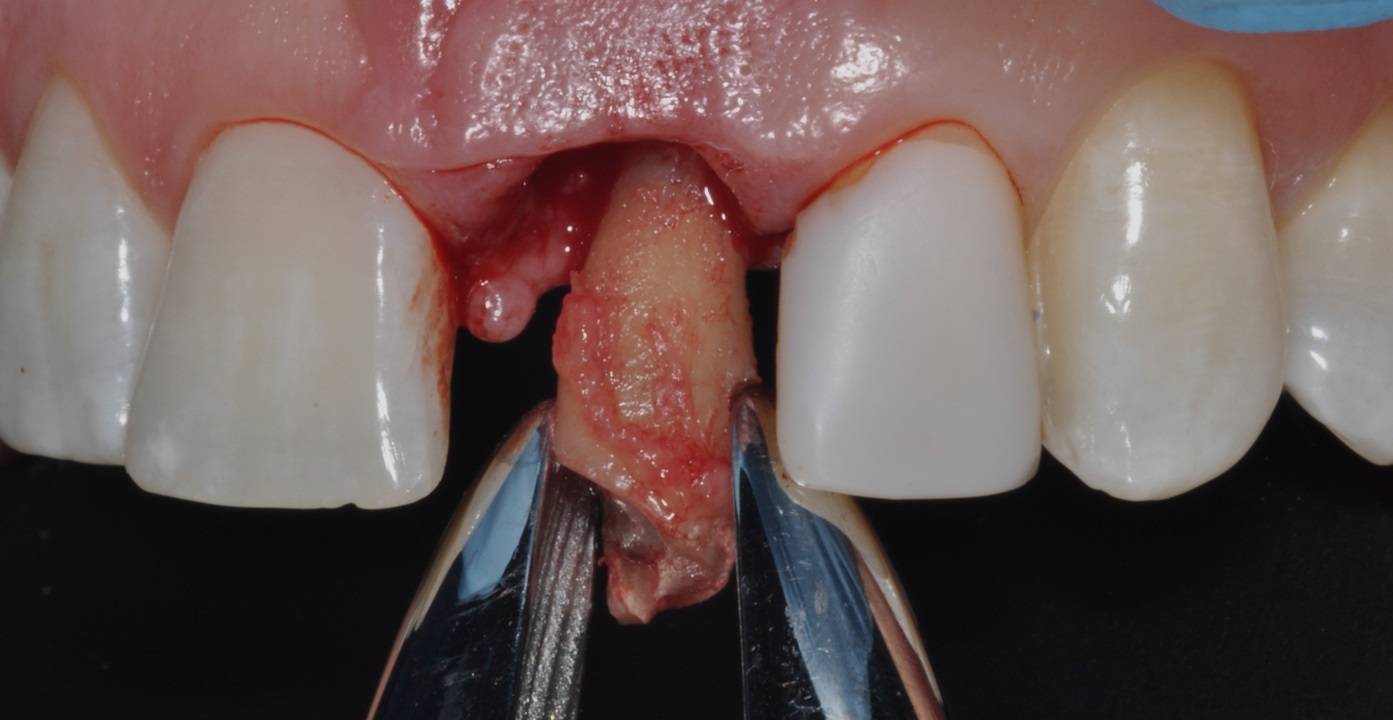

04/16 - Extraction of tooth root 21